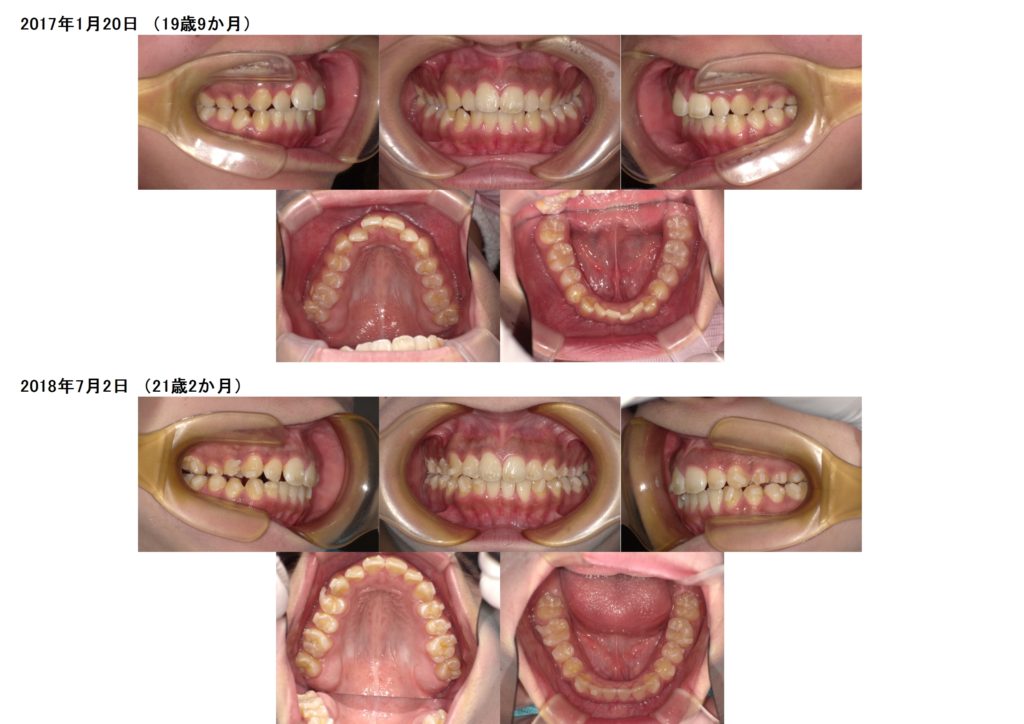

今回は、叢生(ガタガタ歯並び)、噛み合わせの治療をマウスピース、アライナーを使用した治療例になります。

上下の写真を見比べてみると上下の顎の土台をしっかりと整ったのが分かると思います。

特に、上のアーチの形が変わったのが分かりますよね☆

アタッチメントを着けて、しっかりと動かしています。